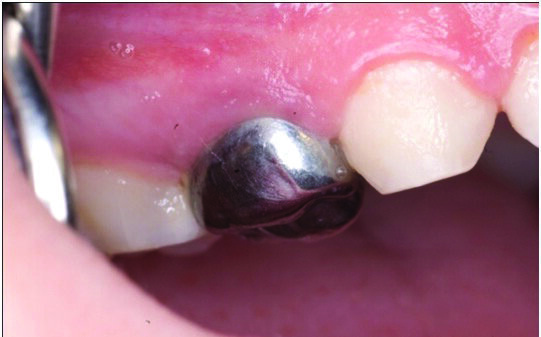

Primary tooth decay management represents a challenge for those who dentally care for children, whether they are general dental practitioners (GDPs) or specialists in paediatric dentistry. For the past 5 decades, the dental literature in the USA and Europe had advocated treating the deep carious primary molar in using the conventional “drill and fill” philosophy. That is, give local anaesthesia (LA) to the child by injection to anaesthetise the tooth, drill the carious tissue out (often after placing a rubber dam-Figure 1) using a high and slow speed drill (Figure 2), restore the primary tooth with a restorative material (often a preformed stainless steel crown or SSC) after carrying out pulp therapy (Figure 3). Although aesthetic crowns are available for primary teeth, they are very expensive and the SSC remains the crown of choice for the carious primary molar (6,7).

Figures 3 (a, b, c, d): The conventional specialist paediatric dentist approach: The SSC is sized up and trialed (Figure 3a), The rubber dam is removed and the SSC is cemented with a glass ionomer (Figure 3b). Figures (3 c & d) show upper and lower arches restored conventionally with SSCs using LA, rubber dam & high speed drills. Compare these with the teeth in Figure 10